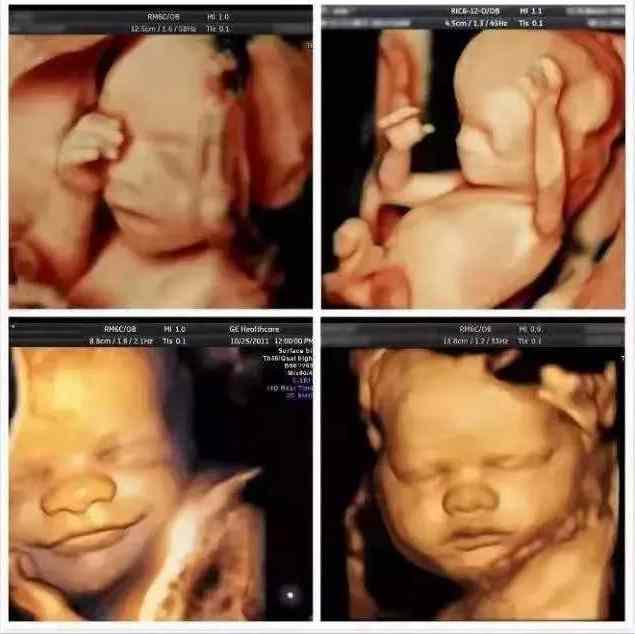

A:四维彩超的全称是四维彩色超声诊断仪,是世界上先进的彩色超声设备。四维彩超能够表面成像,更加清晰的筛查胎儿在子宫的状态,筛查胎儿的体表以及手、脚、心脏、血管等部位是否有异常,提供准确的科学依据,及早发现,及早作出解决方案。

A:四维彩超除了是准妈妈和BB的“第一次”见面,能够看到ta在肚子里或活泼或文静的可爱模样,更重要的是能够监测到胎宝宝的健康情况,进行排畸检查,所以也叫胎儿畸形筛查,是孕期特别重要的一次超声检查。

可以检查到胎儿在宫内是否缺氧,肢体运动、胎儿的吞咽动作等,能够很好的看到胎儿在母体内的活动状况。

安琪妇产医院超声科采用美国进口的GE-E8高清四维彩超,可直观、立体、多方位观察孕妇宫内胎儿的活动图像、生长发育情况,高清显示腹中宝宝的实时动态“动画”,直观了解宝宝的一举一动。